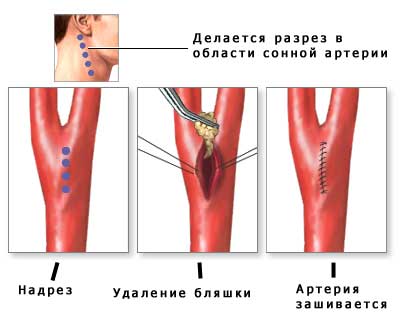

Для восстановления нормального просвета артерий шеи применяются следующие хирургические процедуры:

- Каротидная эндартерэктомия – наиболее распространенный метод хирургического лечения. Во время операции хирург делает разрез в области сонной артерии, где по результатам обследования выявлен стеноз. Затем удаляется атеросклеротическая бляшка или тромб, после чего артерия и мягкие ткани зашиваются. Каротидная эндартерэктомия рекомендуется пациентам с уровнем стеноза 50-60%.